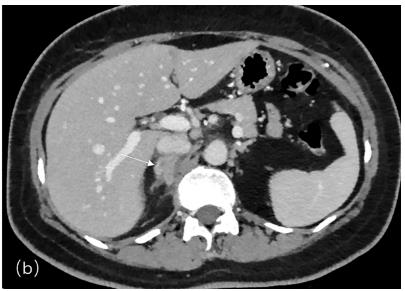

Fig.1 Adrenal mass with heterogeneous enhancement and multiple para-aortic lymph nodes on CT imaging (arrow).1